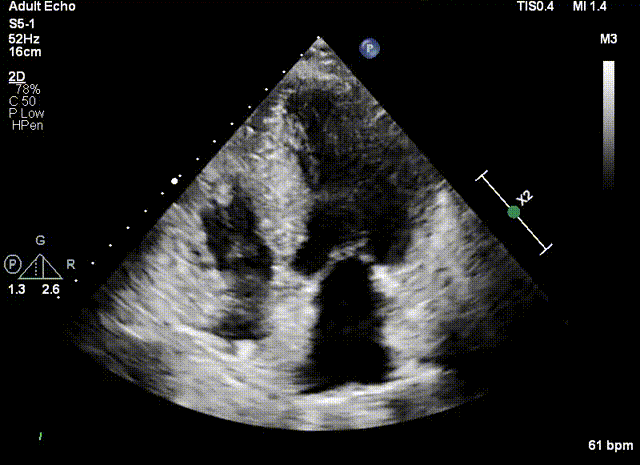

三位患者均患肥厚型梗阻性心肌病多年,因药物治疗效果不佳而到浙江大学医学院附属第二医院就诊。超声提示三位患者的室间隔呈非对称增厚,造成左室流出道梗阻。经团队评估决定进行超声引导下Liwen术式对室间隔进行消融。

患者是一位58岁的女性。超声提示患者室间隔最大厚度为26.3mm,静息状态左室流出道压差为118mmHg,负荷状态下为233mmHg。